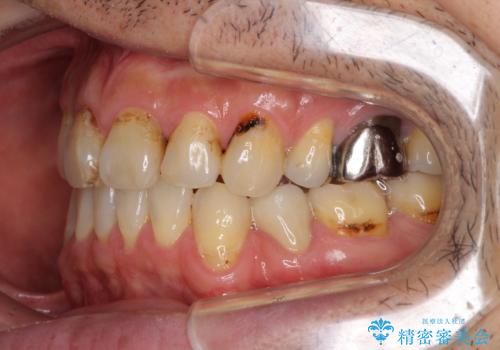

- むし歯による奥歯の痛みを気にして来院された患者様です。

神経にまでむし歯の及んでいる歯や、既に根管治療がされている歯に痛みがあったため、まずは根管治療を行うこととしました。

その後、以前行った抜歯矯正の後戻りをインビザライン・ライトにより改善し、むし歯や銀歯はオールセラミッククラウンにて補綴治療することとしました。

痛みは速やかに引き、銀歯や黒く変色したむし歯がセラミッククラウンで自然な色合いに仕上がり、患者様には大変満足していただきました。